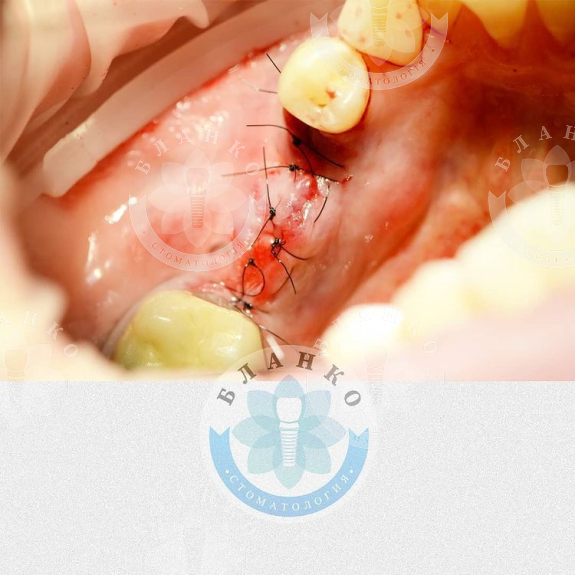

💎Міст знятий, видалений безнадійний зуб, на його місце одномоментно встановлено імплант ICX (Німеччина),проведена аугментація (нарощування) кісткової тканини та ясна.